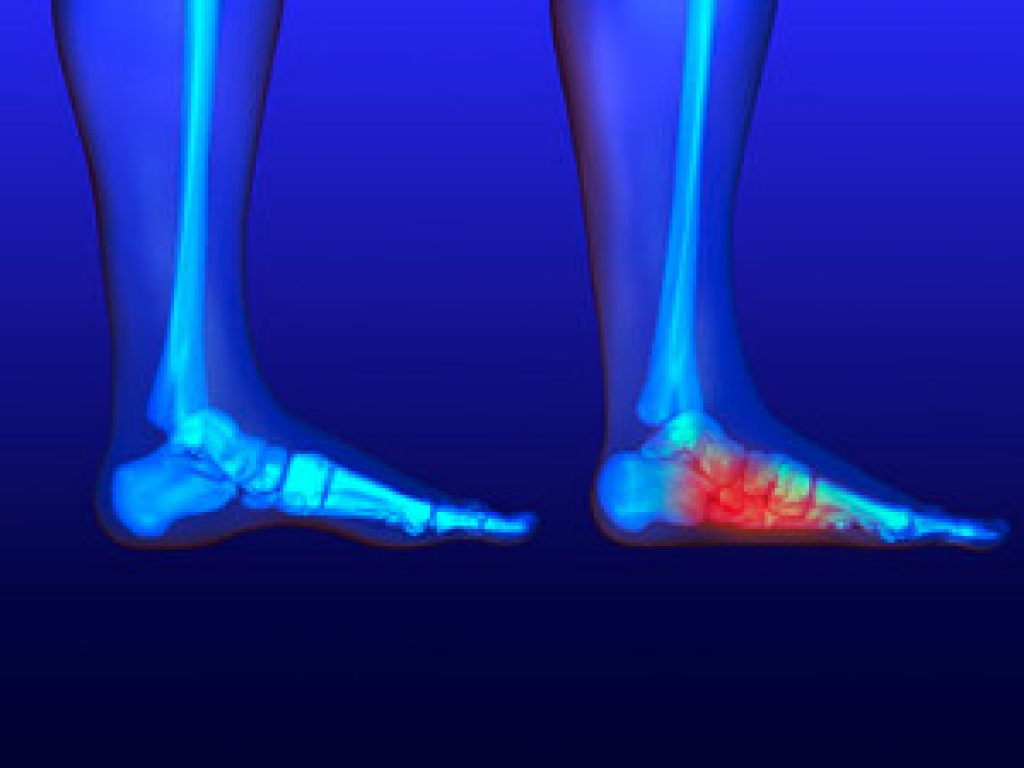

Osteoarthritis of the Ankle

Ankle osteoarthritis is a relatively uncommon condition often arising years after an ankle injury that damages the cartilage. Unlike other forms of arthritis, it tends to affect younger individuals, especially those with a history of trauma to the joint. Excess weight can worsen the condition by increasing stress on the ankle and accelerating cartilage deterioration. Symptoms of ankle osteoarthritis include pain, stiffness, and swelling in the joint, which can increase with activity and improve with rest. Patients may also experience a reduced range of motion and a feeling of instability in the ankle. Diagnosis typically involves a physical examination, patient history, and imaging tests, such as X-rays or MRI scans, to assess cartilage damage and joint space narrowing. Treatment focuses on managing symptoms and improving joint function. Conservative approaches include weight management, targeted stretching exercises, anti-inflammatory medications, and orthotics. In severe cases, surgical options like ankle arthroscopy, fusion, or joint replacement may be considered to alleviate pain and restore mobility. If you have persistent ankle pain, it is suggested that you schedule an appointment with a podiatrist for a proper diagnosis and treatment.

Ankle osteoarthritis is a relatively uncommon condition often arising years after an ankle injury that damages the cartilage. Unlike other forms of arthritis, it tends to affect younger individuals, especially those with a history of trauma to the joint. Excess weight can worsen the condition by increasing stress on the ankle and accelerating cartilage deterioration. Symptoms of ankle osteoarthritis include pain, stiffness, and swelling in the joint, which can increase with activity and improve with rest. Patients may also experience a reduced range of motion and a feeling of instability in the ankle. Diagnosis typically involves a physical examination, patient history, and imaging tests, such as X-rays or MRI scans, to assess cartilage damage and joint space narrowing. Treatment focuses on managing symptoms and improving joint function. Conservative approaches include weight management, targeted stretching exercises, anti-inflammatory medications, and orthotics. In severe cases, surgical options like ankle arthroscopy, fusion, or joint replacement may be considered to alleviate pain and restore mobility. If you have persistent ankle pain, it is suggested that you schedule an appointment with a podiatrist for a proper diagnosis and treatment.

Arthritis can be a difficult condition to live with. If you are seeking treatment, contact Pasquale Cancelliere, DPM from Candria Foot and Ankle Specialists. Our doctor can provide the care you need to keep you pain-free and on your feet.

Arthritic Foot Care

Arthritis is a term that is commonly used to describe joint pain. The condition itself can occur to anyone of any age, race, or gender, and there are over 100 types of it. Nevertheless, arthritis is more commonly found in women compared to men, and it is also more prevalent in those who are overweight. The causes of arthritis vary depending on which type of arthritis you have. Osteoarthritis for example, is often caused by injury, while rheumatoid arthritis is caused by a misdirected immune system.